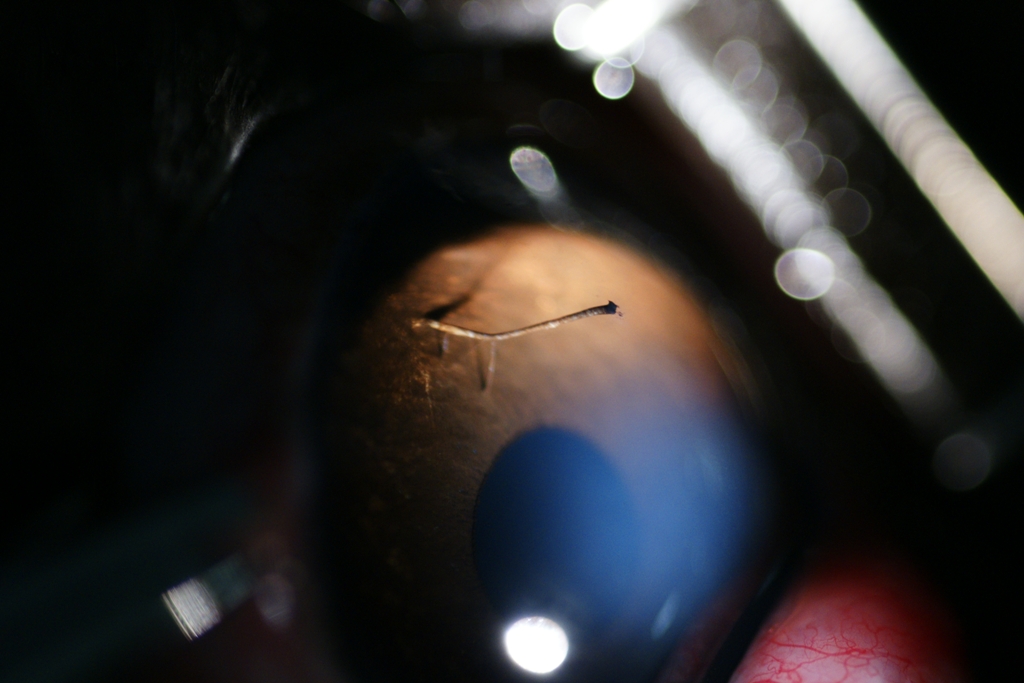

Persistance de membrane pupillaire chez un chaton (le truc bizarre à la droite du point lumineux). C'est complètement bénin

- 64530 (386.39 Kio) Consulté 2728 fois